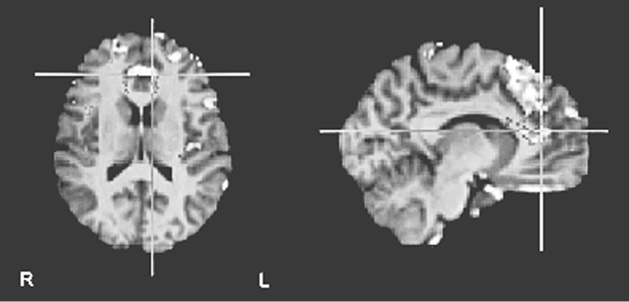

«Не уверен», как и предполагалось, активизировала переднюю поясную кору – своего рода нейронный сигнальный свет, вспыхивающий при внезапном появлении на горизонте чего-то нового и загадочного (рис. 8.1c (i) и (ii)).

Рис. 8.1c (i – вверху) и 8.1c (ii – внизу). Повышение активности во фронтальной части поясной извилины и в верхней лобной извилине при оценке утверждений, не поддающихся проверке («не уверен»). Рис. 8.1c (i) показывает разницу в активности по сравнению с картиной восприятия суждений, вызывающих доверие. Рис. 8.1c (ii) показывает разницу с картиной восприятия суждений, вызывающих недоверие (по материалам Харриса и др., 2008)